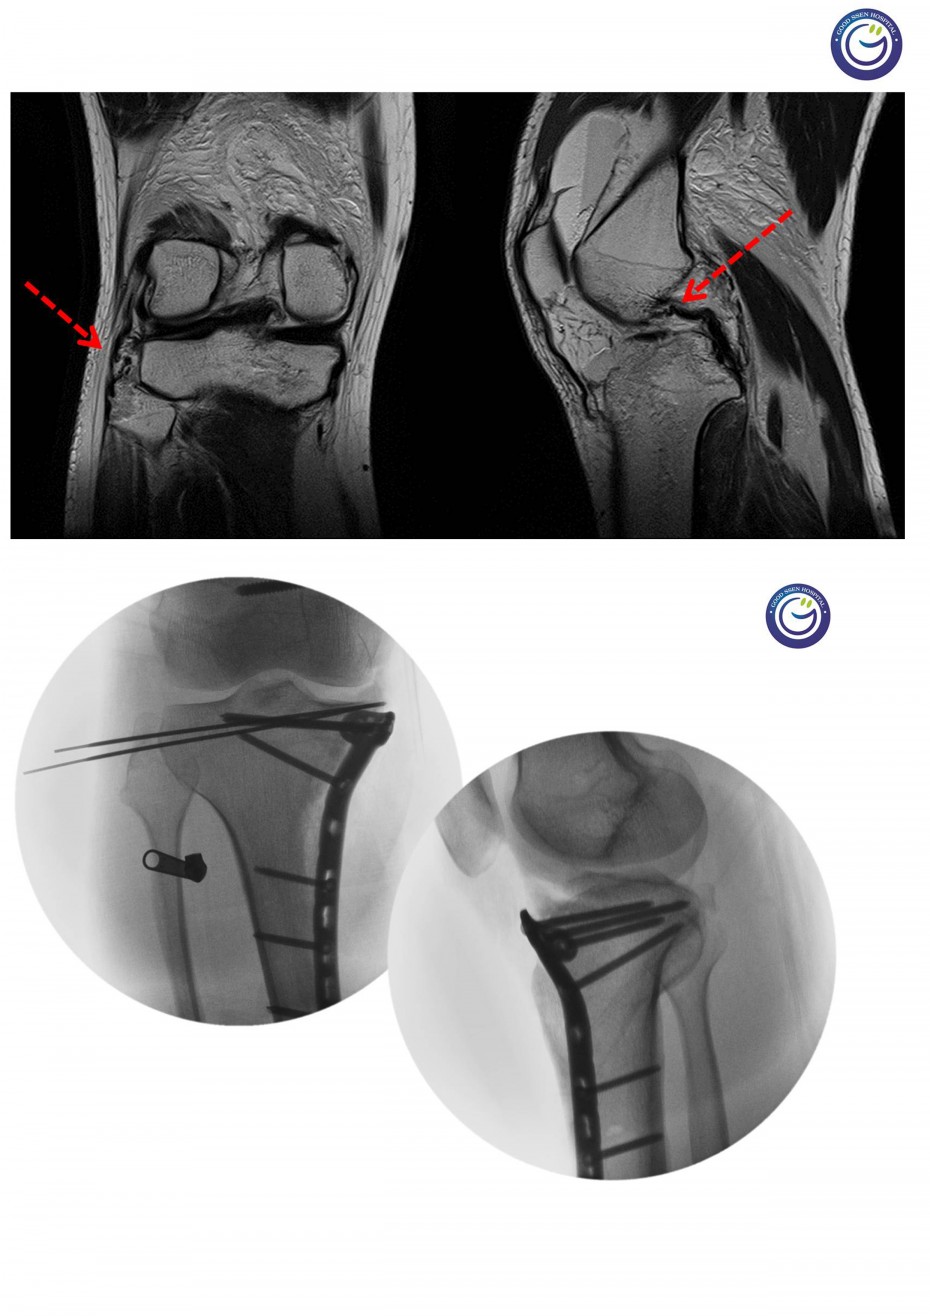

관절을 침범하는 심한 분쇄골절

절개없이 고정하는 최소침습적 고정방법 (MIPO)